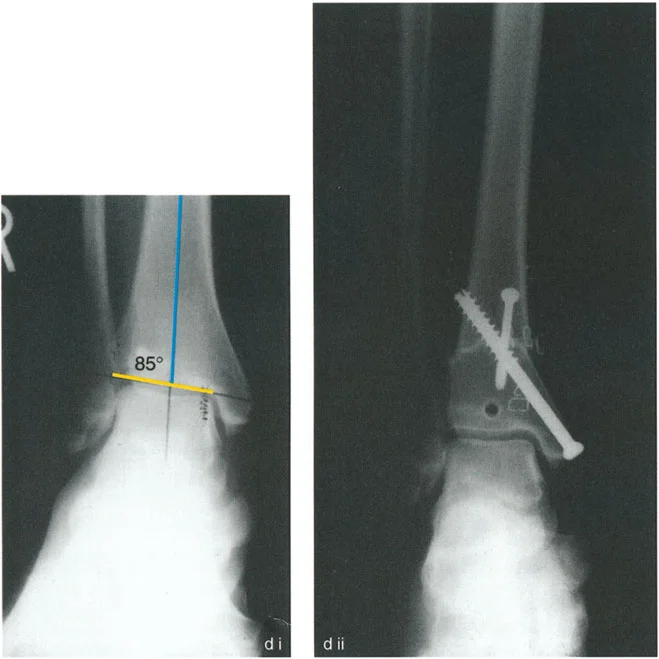

* الأشعة السينية الجانبية والامامية الخلفية للكاحل: تُظهر هذه الصور تفاصيل مفصل الكاحل نفسه، بما في ذلك زاوية القصبة الأمامية البعيدة (ADTA) وزاوية القصبة الوحشية البعيدة (LDTA)، وهي زوايا حاسمة لتحديد التشوه في المستويين الأمامي والسهمي.

* رسم المحاور الميكانيكية والتشريحية: لتحديد نقطة مركز دوران التشوه (CORA)، وهي النقطة التي يجب أن تتم عندها الجراحة لتصحيح التشوه بأقل قدر من المضاعفات.

• قواعد بالي لقطع العظم:

1. القاعدة الأولى: عندما يمر قطع العظم ومحور تصحيح الزاوية (ACA) عبر CORA، يتم تحقيق تصحيح زاوي نقي دون أي إزاحة.

2. القاعدة الثانية: عندما يمر ACA عبر CORA، ولكن قطع العظم يتم في مستوى مختلف (غالبًا ما يكون ضروريًا لتوفير مساحة كافية للتثبيت)، يتم تحقيق تصحيح زاوي نقي، ولكن أطراف العظم ستنزاح في موقع قطع العظم. يجب على الجراح توقع هذه الإزاحة وإدارتها.

3. القاعدة الثالثة: إذا كان ACA وقطع العظم في نفس المستوى، ولكن لا يمر أي منهما عبر CORA، فسيحدث تشوه إزاحة (ترجمة) غير مرغوب فيه. يتطلب هذا الأمر من الجراح إجراء إزاحة متعمدة للقطعة العظمية البعيدة أثناء التصحيح الزاوي لإعادة محاذاة المحور الميكانيكي.